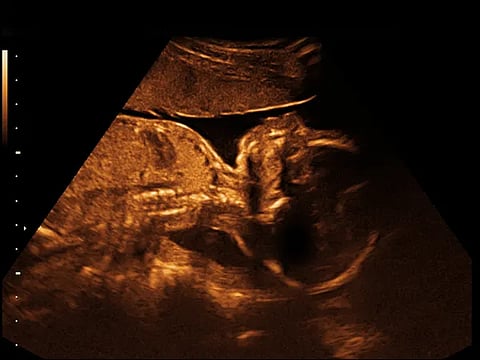

De acuerdo con la información difundida en redes sociales, el pasado 6 de mayo una mujer embarazada, identificada como Itzel M., acudió al área de urgencias del hospital debido a complicaciones con su embarazo. Sin embargo, según relatan sus familiares, no recibió atención médica oportuna debido a la ausencia de personal ginecológico.

La paciente habría regresado horas después al hospital, donde finalmente le informaron que el producto ya no presentaba signos vitales. La denuncia refiere que pese al estado crítico de la madre, tampoco se le brindó atención inmediata, lo que puso en riesgo su vida.